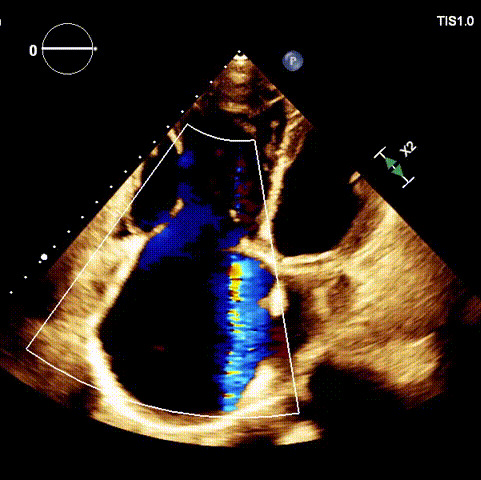

術前超聲

1.二尖瓣位機械瓣位置及功能未見異常;2.雙房及右室明顯擴大(左房收縮容積115ml,右房收縮容積370ml,右室中段左右徑65mm,右室FAC37%),下腔靜脈及冠狀靜脈竇擴張(下腔靜脈直徑44mm,冠狀靜脈竇直徑22mm);3.極重度三尖瓣反流(FTR 6+)。

入路血管最小平均徑約14.5mm,入路血管無嚴重迂曲,無鈣化。